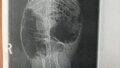

今回の原因について、検査では

・胆のう

・肝臓

・腫瘤

なども指摘されましたが、今回は「胃腸の不調」が主な原因の可能性が高いと感じています。